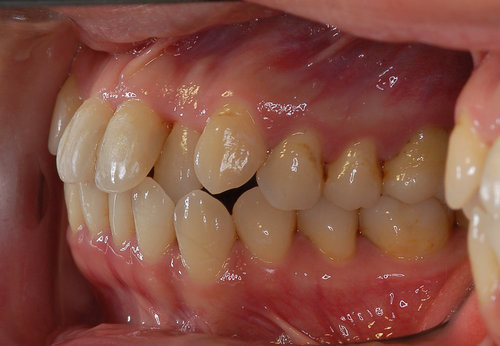

双颌前突表现为上下牙弓和前牙均向前突出,严重者上下嘴唇不能自然闭合,形成“开唇露齿”。双颌前突影响外貌美观,也影响口腔咀嚼功能,终对身体健康不利,双颌前突必须得到改善。那么双颌前突应该怎么办?下文为大家揭晓治疗双颌前突的方法。

1、轻度或中度双颌前突或双牙弓前突者,内收上下前牙,同时矫治深覆牙合。

2、严重上下颌前突者,需做外科正畸手术。